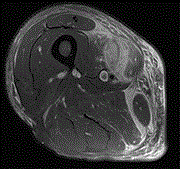

Spontaneous rupture and hematoma of the sartorius muscle secondary to rivaroxaban therapy

Javier Ardebol and others

Journal of Surgical Case Reports, Volume 2020, Issue 4, April 2020, rjaa090, https://doi.org/10.1093/jscr/rjaa090